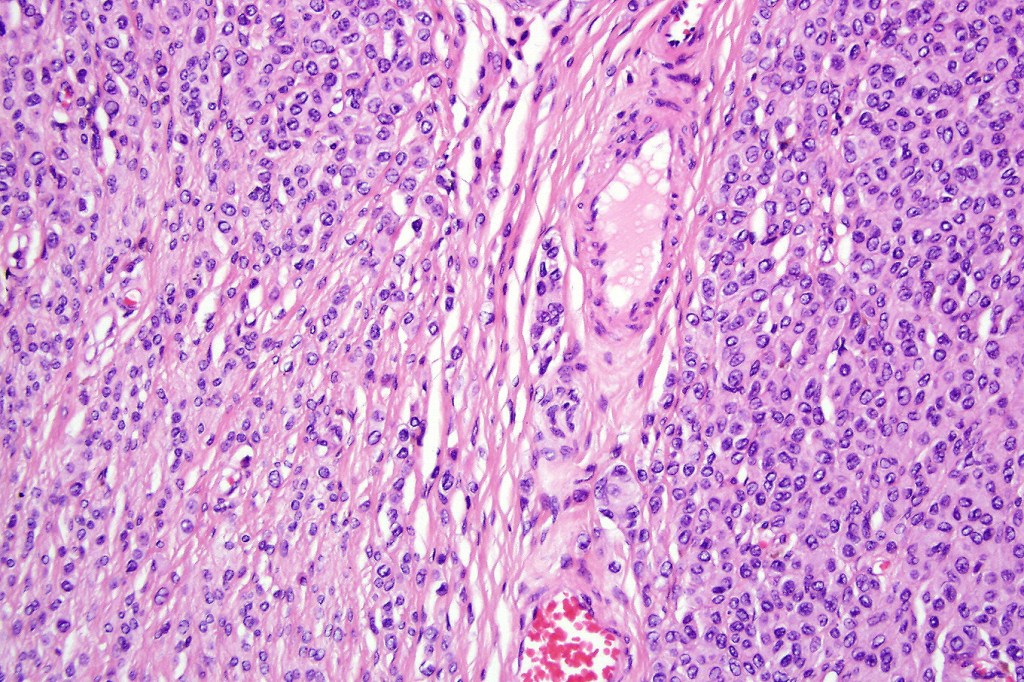

•The nodule generally merges with the adjacent nevus but sometimes it can be sharply circumscribed

•It is hypercellular and most often composed of epithelioid cells showing little pleomorphism & only occasional mitoses

•Nuleoli are small

•Intracytoplasmic pseudo-inclusions

•The constituent cells are generally larger than the adjacent nevus cells

•Some examples show more marked pleomorphism with prominent nucleoli and increased mitotic activity but abnormal mitoses are not a feature. These are not associated with any sinister biological potential

•Absence of necrosis, hemorrhage or Pagetoid spread in the overlying epidermis

•Spindle cell, small blue cell, blue nevus-like features, Spitzoid & proliferative nodules with mesenchymal differentiation (myofibroblastic, chondroid & osteoid) can be seen